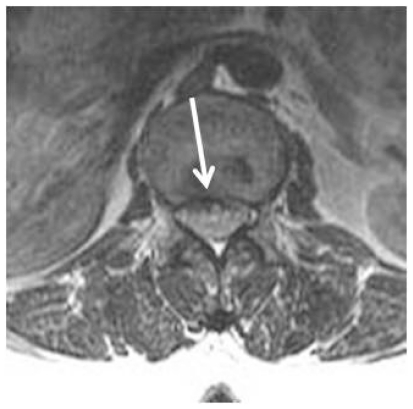

Figure 6.

39 year-old female with Guillain-Barré syndrome secondary to systemic lupus erythematosus. Contrast – enhanced fat suppressed sagittal T1-weighted MR imaging shows marked contrast enhancement of thickened nerve roots of cauda equina and conus medullaris (arrows).